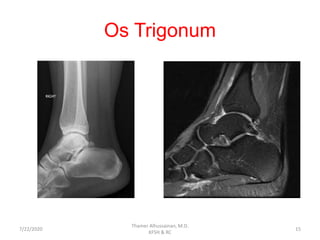

Os Trigonum

• It is the lateral border for the FHL grove in the back

of the talus

• Between the ages 8-11 yrs, the secondary

ossification center appears, and it fuses within 1

year.

• Injury to Os Trigonum occurs with forceful plantar

flexion.

• Clinical and radiological evaluation.